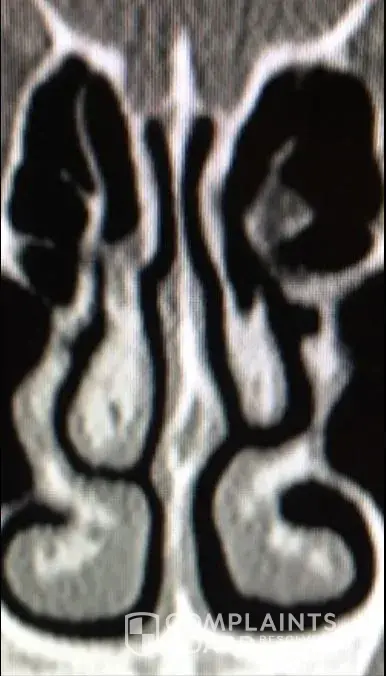

For people reading this, I have included x-ray images of the inside of my nose, before and after my surgery with him. As you can see from these images, my nasal airway was equally open on both sides, before surgery, and the septoplasty didn't need to be done. By performing it, he severely narrowed the right side of my nasal airway.

Dr Raviv performed two surgeries on me: endoscopic sinus surgery (where they widen the sinus passages), and septoplasty (where they straighten the septum). The septoplasty, however was completely unnecessary, and severely narrowed the right side of my nasal airway. For people reading this, I have included x-ray images of my sinuses, before and after my surgery with Dr. Raviv. As you can see from the surgery, my airway was much more open, and equal on both sides, before my surgery with him.